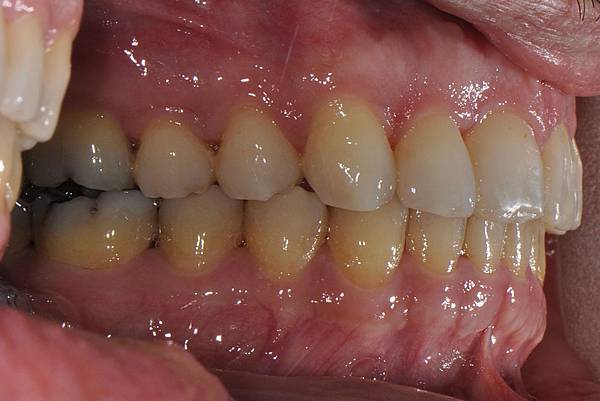

台灣的牙科醫療品質, 連外國人都說讚!此案例為深咬合併二級咬合 林醫師藉由正中上顎骨釘(HPPG technique)做上顎全齒列後移改善暴牙 讓本來五官就相當立體的艾先生,笑起來更燦爛了! 治療前/治療後-以上案例由林昇進醫師提供 分享到